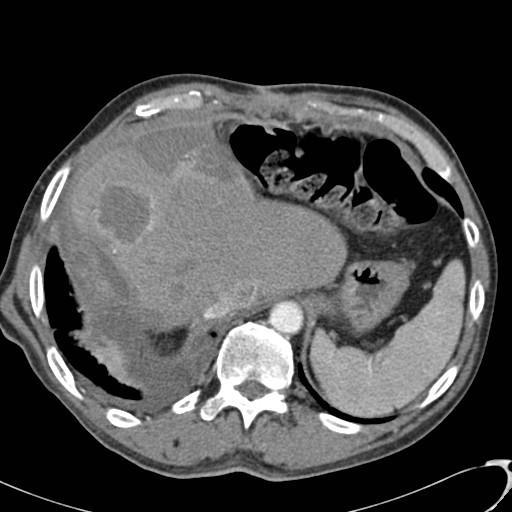

经皮消融治疗技术一般是在超声或CT引导下入路。射频消融具有可冷却的电极头和扩展电极。术中需要有CT监视,邻近血管旁电极有消融补偿。术后安排影像学随访。 肝脏转移癌的消融是一种治愈的手段吗?答案是肯定的。外科手术再也不是唯一的治愈手段,为了达到治愈的目的消融治疗也是一个选择。如何定义所谓的治愈治疗呢?其实根据外科文献,即使是外科手术5年的存活率也不是很高,所谓治愈性切除后的5年生存率也不过是40%,而10年生存率也就10%。治愈的定义是无瘤生存5年以上。 问题是什么时候消融是治愈性的?什么时候病变可以被治愈?达到治愈你需要做些什么呢? 有限的肝转移数目,如1~4个;肿瘤的体积不能太大,如1~6厘米;没有腹腔内或肝外,包括肝门部转移等。都是消融治愈的条件。另外,不适合其它任何治疗,以前进行过肝切除,以前进行化疗异常。后续治疗包括消融后立即(10天内)进行化疗(FOLFOX/FOLFIRI)。 2/3一次完全消融没有复发和新位置出现。1/3 出现新位置病灶,包括肺转移,但这些也可以通过射频消融成功进行治疗。 为了达到治愈的目标你需要尽早发现肝转移的出现,对发现的病变进行正确的鉴别;准确的消融,强调安全的消融边界,术中需要CT监测。